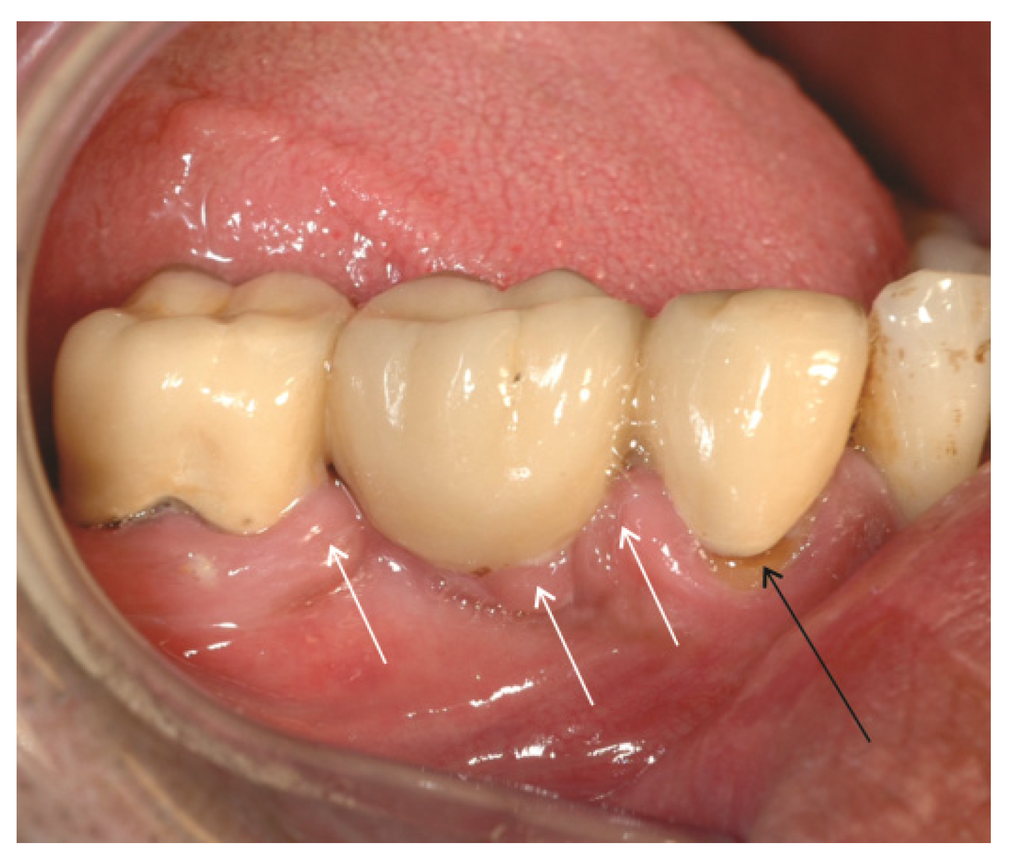

Dental restorations affect the composition of the biofilm in many ways. There will always be steps, gaps or groves between tooth and restoration (Figure 3). These will complicate mechanical biofilm removal and alter the chemical balance in the biofilm in the region (Figure 4) [29,30]. Restorations differ from enamel with regard to surface roughness, surface energy and chemical composition [29,30,31,32,33]. Most adults have at least one dental restoration and the role of biofilm related infections related to the restoration as opposed to primary oral infections is not easily distinguished.

Figure 4. Secondary caries at the crown margin (black arrow) caused by accumulation of biofilm in the crevice between crown and tooth. Hyperplastic gingiva (white arrows) due to increased plaque accumulation in the connector area of the fixed partial denture. The connector area of the bridge has a bulky design which complicates interdental hygiene (photo: Marit Øilo).